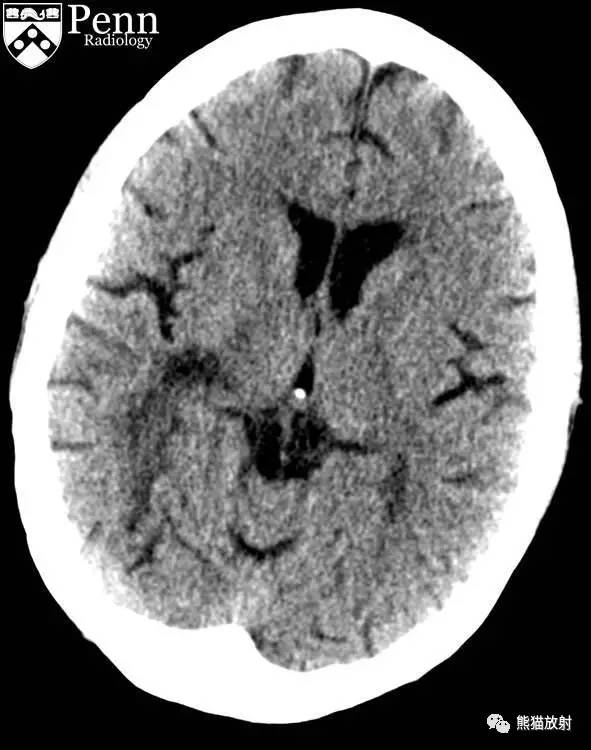

CT平扫表现:左额叶白质见片状低密度,经胼胝体累及右额叶白质。

CT:在双侧顶叶、枕叶皮层下白质、深部白质束和胼胝体可见多发融合的密度减低区。无占位效应,灰质密度未见明显异常。

CT:皮质下和侧脑室周围白质密度减低,但无占位效应。